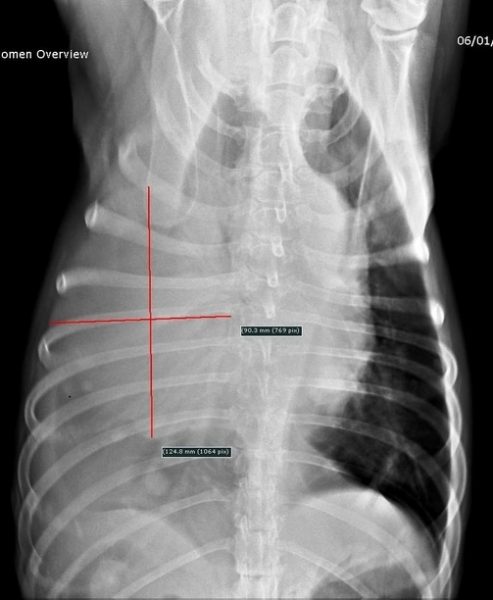

Un examen radiographique est réalisé sur animal vigile. Le coude gauche présente une dégradation arthrosique déjà avancée que l’on retrouve également sur le coude droit. Une déformation des tissus mous est visible en regard de la portion caudale de la scapula. L’articulation scapulo-humérale ne présente pas d’anomalie, seule la scapula présente des modifications de son architecture sur sa face interne avec une corticale effacée, une association d’ostéolyse et d’ostéoproduction (fig. 2 et 3).